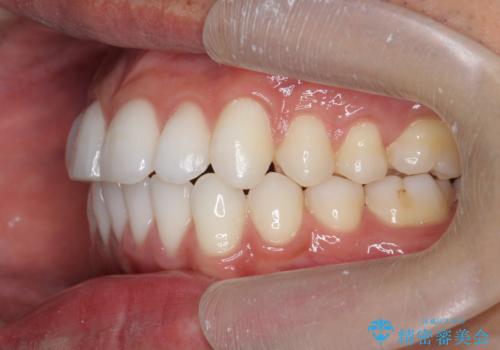

- 前歯の噛み合わせの開きの改善を求めて来院されました。

奥歯はほとんど動かさず(奥歯の噛み合わせはほとんど変えず)前歯のIPR矯正でガタつき前突感(出っ歯感)の改善を計画します。

ほとんど前歯のみの矯正治療であることからトータル14枚のマウスピースで並べるインビザラインライトによる治療を行います。

インビザラインライトは全14枚のマウスピースで行う軽度なガタつきなどの改善を目的とする矯正治療です。(約3.5ヶ月)

今回の治療では追加でマウスピース治療を行なったため、半年弱の治療期間となりました。